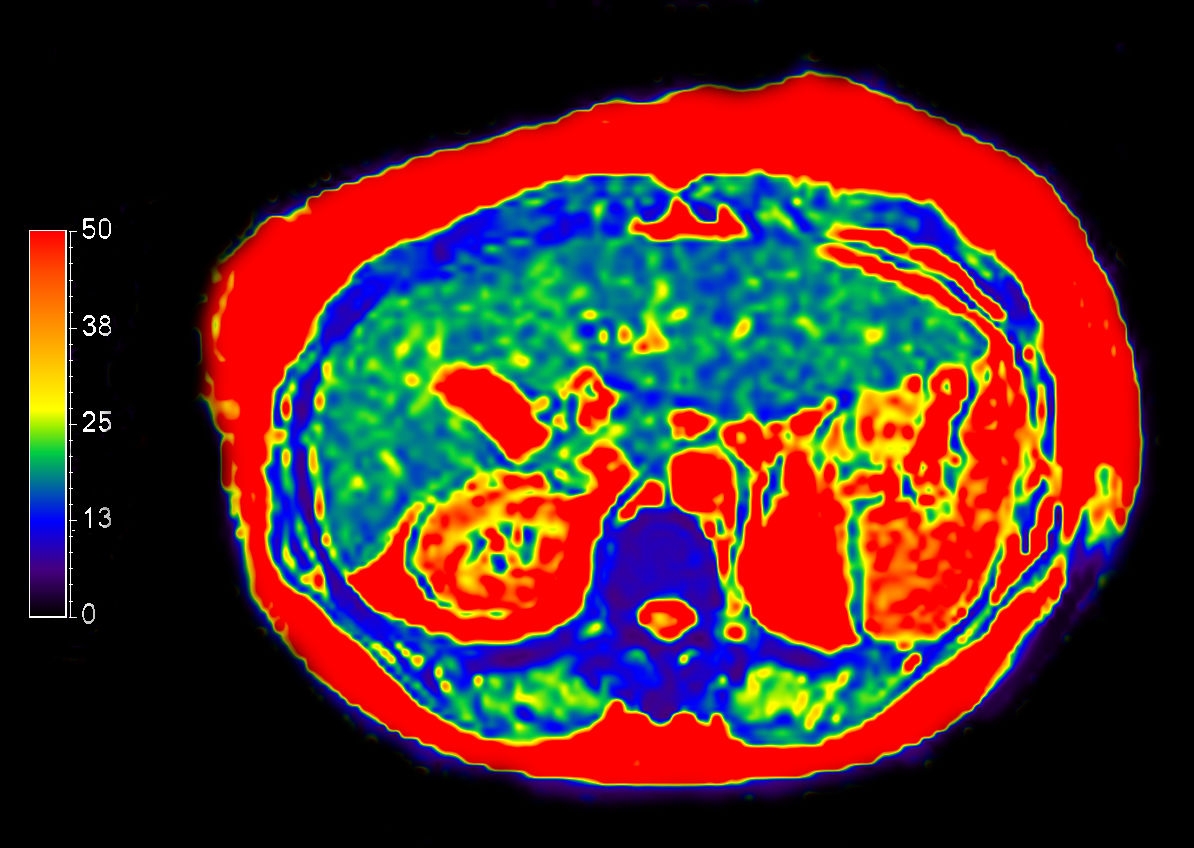

Liver ExamCard including single breath hold 3D mDIXON Quant for non-invasive liver fat quantification of the whole liver with high accuracy (± 3.5%) and reproducibility (± 1.4%)1. And MR Elastography for a non-invasive assessment of differences in tissue stiffness of the liver. Image processing is fully integrated at the scanner with automated calculation of Elastograms, reflecting tissue stiffness in kPa and statistical confidence map for reliability assessment.

MR Elastography (SE-EPI, 4 slices)

MR Elastography (SE-EPI, 4 slices) (Stiffness Map)

MR Elastography (SE-EPI, 4 slices) (processing)